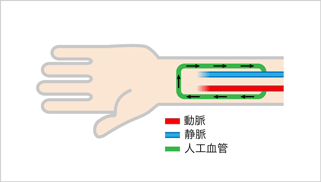

人工血管内シャント

ご自身の静脈が細い、詰まっているなどシャントに適さない場合は、ご自身の静脈の代わりに人工血管を移植してシャントを作製します。人工血管は合成素材で出来た直径4mmから6mmのチューブです。自己静脈が乏しい場合でも十分な血流を有するシャントを作製することが出来る利点がありますが、自己静脈内シャントと比較すると閉塞と感染に注意が必要となります。

人工血管による内シャントでは、通常60-120分程度の手術時間で、局所麻酔下に行います。